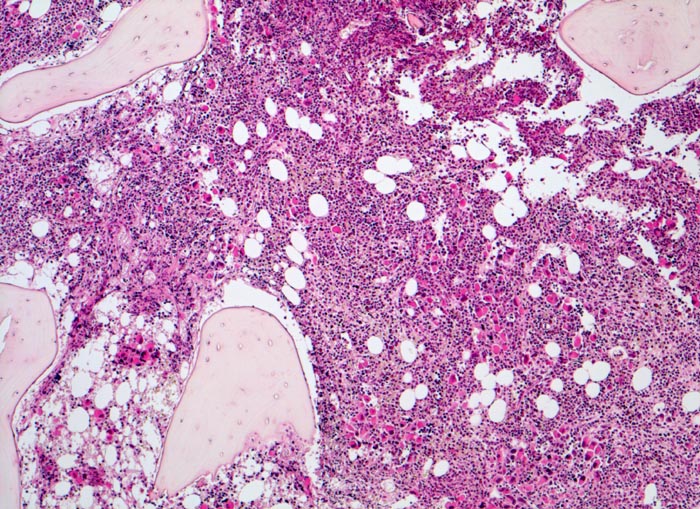

Morphologie

Morphologische Merkmale:

• Osteosklerose: verplumpte und breite Knochenbälkchen.

• Kollagenfibrose.

• Dilatierte Sinusoide mit intrasinusoidaler Blutbildung.

• Vermehrung von atypischen, in Gruppen liegenden Megakaryozyten mit abnorm lobulierten Kernen.

• Nacktkernige (zytoplasmaarme) und vergrösserte Megakaryozyten.

• Hyperplastische ausreifende Myelopoese.

• Hypoplastische Erythropoese.

• Retikulinfaserfibrose des Marks vorhanden aber in der HE Färbung schwierig quantifizierbar.